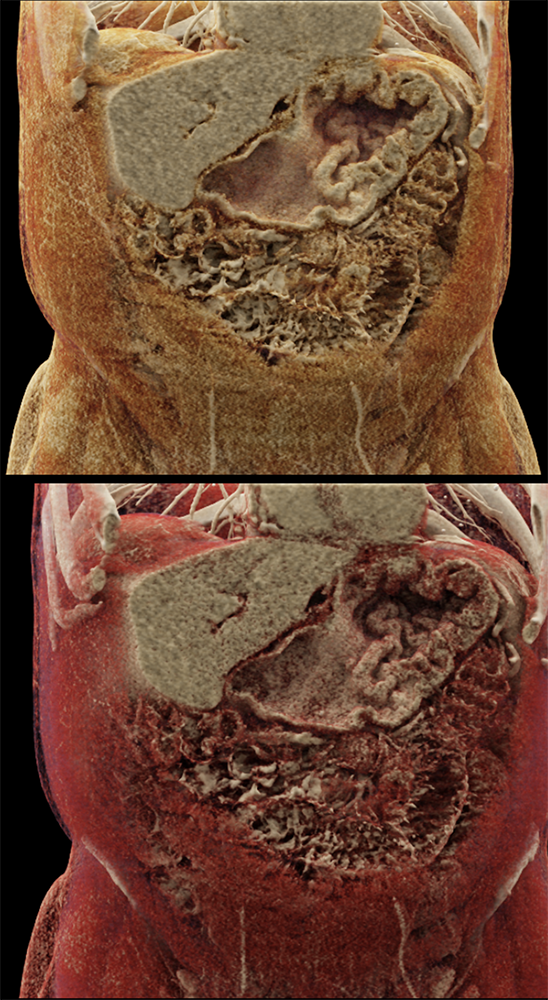

Watermelon stomach (WMS), or gastric antral vascular ectasia (GAVE) ![]() |

“Gastric antral vascular ectasia primanily affects women (9:1 female-to-male ratio) aged 56-76 years, and is associated with liver cirrhosis (37%) and achlorhydnia (35%). The usual symptoms are iron-deficiency anemia and melena due to chronic gastrointestinal bleeding from the dilated, superficial, and easily traumatized vessels. Antrectomy is curative, but endoscopic treatment with heat probes or lasers has shown promise.” Gastric antral vascular ectasia ("watermelon stomach"): radiologic findings. Urban BA, Jones B, Fishman EK, Kern SE, Ravich WJ. Radiology. 1991 Feb;178(2):517-8. |

“In our patient, the findings of prominent mucosal folds extending from the pylonic channel on upper gastrointestinal series and the thickened antral wall on CT scans correlate well with the known pathologic appearance of gastnic antral vascular ectasia. Histologically, antral thickening results from a combination of foveolar and fibromuscular hyperplasia. Grossly, the antral fold prominence appears to result from bunching of the mucosa in the thickened, hypercontractile antrum.” Gastric antral vascular ectasia ("watermelon stomach"): radiologic findings. Urban BA, Jones B, Fishman EK, Kern SE, Ravich WJ. Radiology. 1991 Feb;178(2):517-8. |

“Watermelon stomach (WMS), or gastric antral vascular ectasia, is an uncommon but clinically important cause of chronic occult or overt gastrointestinal (GI) blood loss. Patients typically present with symptomatic anemia and hemoccult positive stools. Although the diagnosis is based primarily on the typical endoscopic appearance, the lesion may be overlooked on initial evaluation or interpreted as "gastritis." Gastric biopsy may be helpful in confirming the diagnosis by showing vascular ectasia, typically without inflammation. WMS is idiopathic but is often associated with autoimmune diseases or cirrhosis of the liver. The majority of patients with classic WMS are elderly and female.” |

“Gastric antral vascular ectasia (GAVE) is a rare entity with unique endoscopic appearance described as "watermelon stomach." It has been associated with systemic sclerosis but the pathophysiological changes leading to GAVE have not been explained and still remain uncertain.” Gastric Antral Vascular Ectasia in Systemic Sclerosis: Current Concepts. Parrado RH et al. Int J Rheumatol. 2015;2015:762546. |